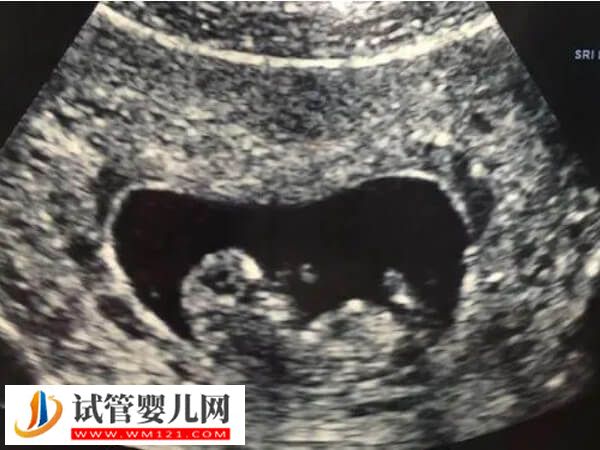

试管婴儿技术早已进入到成熟的阶段,能通过各种不同方法让不孕的女子顺利的拥有健康的宝宝,而且能够达到优生优育的效果,可以减少遗传性疾病的出现,但是与此同时也会有着一些缺点,如下所列: